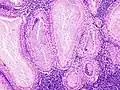

The appearance of this tumor under the microscope is unique. There are cystic spaces surrounded by two uniform rows of oncocytes, which are epithelial cells with abundant, granular, eosinophilic cytoplasm.[7] The cystic spaces have epithelium referred to as papillary infoldings that protrude into them. Additionally, the epithelium has lymphoid stroma with germinal center formation.

Histopathology of Warthin tumor in the parotid gland. Higher magnification of a file "Warthin tumor (1).jpg". H&E stain.

Intermediate magnification micrograph of a Warthin tumor.

High magnification micrograph of a Warthin tumor showing the characteristic bilayered epithelium.